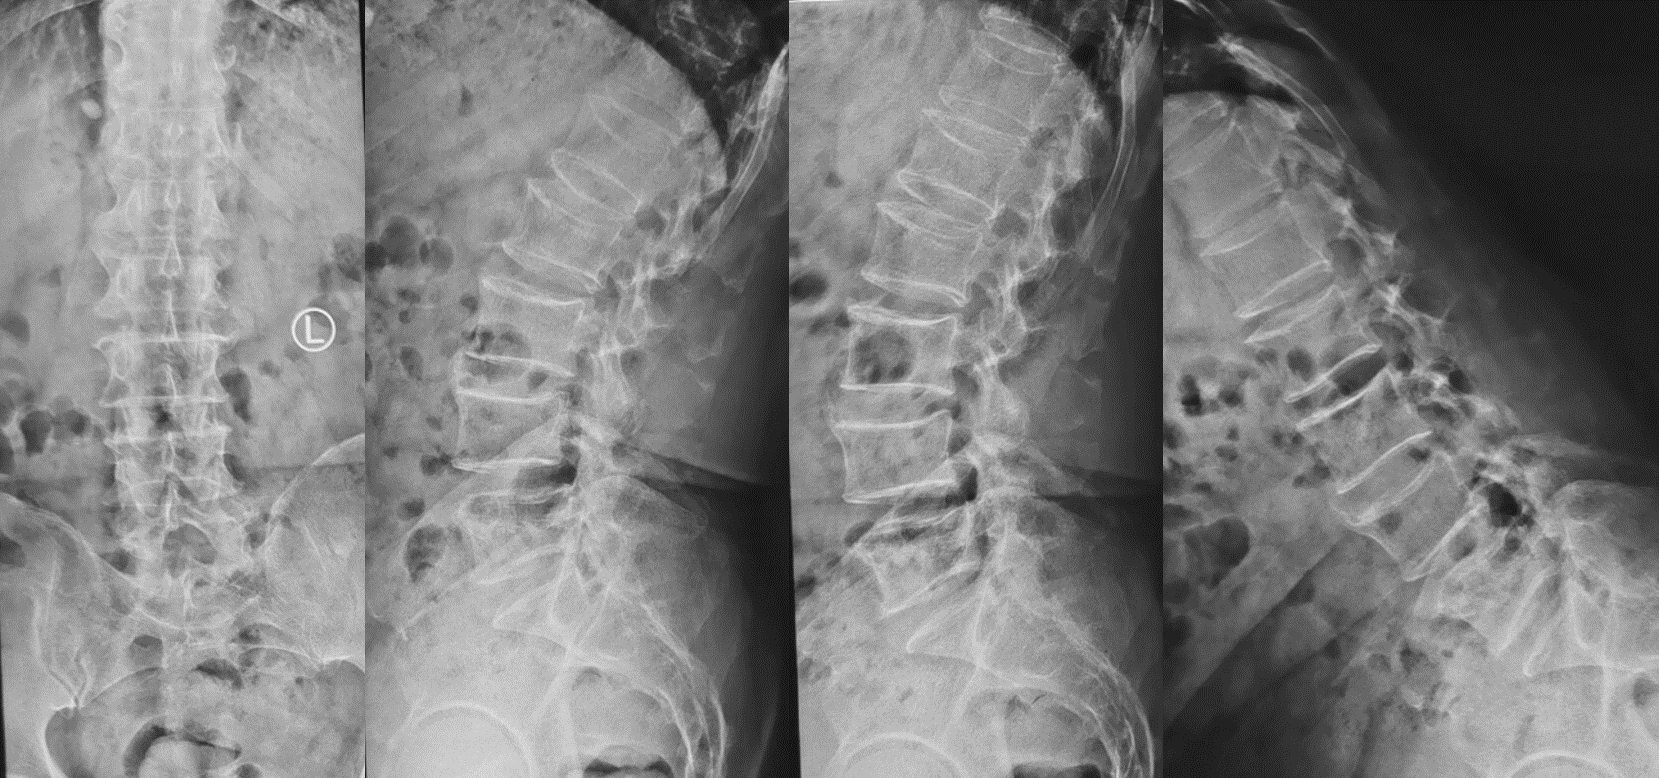

第三例51岁女性患者,因“右下肢放射性疼痛、麻木1年,加重1月余”入院,发病以来反复多次保守治疗无效。入院后经术前讨论、评估,制定治疗方案,行OLIF手术,该病例采用后路经皮椎弓根螺钉内固定。次日患者下地活动,下肢症状消失,疗效满意。

术前影像

术后复查